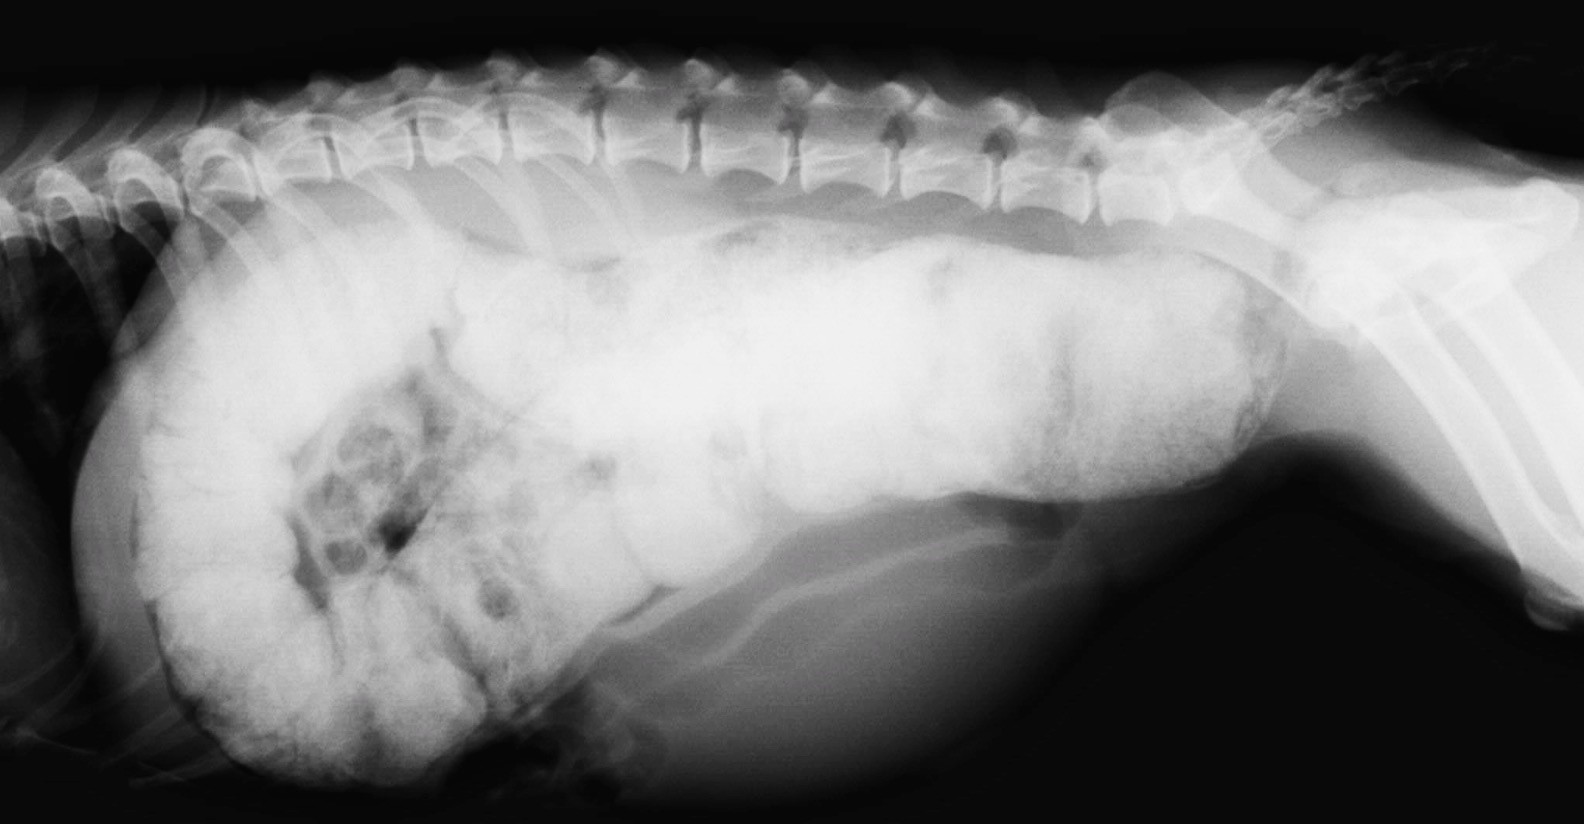

Оберіть рентгенівське зображення відповідно діагнозу.

View this question

Яка викладка (проекція) зображена на знімку:

рентген